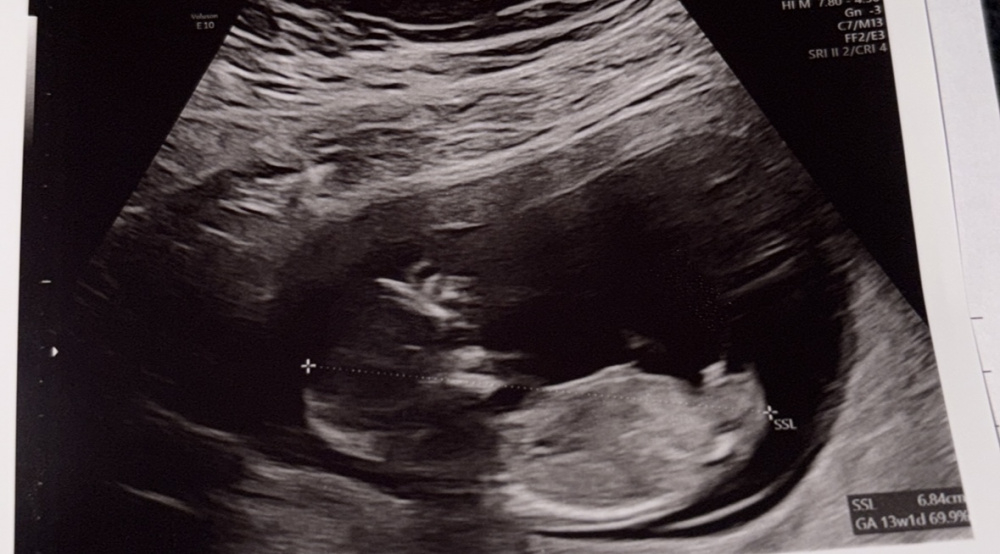

Eindeutig Junge ? 12+5

Hatte gestern bei 12+5 das ETS. Ärztin wollte uns nicht verraten, aber sieht das nicht eindeutig aus ? Oder könnte da evt. Die Nabelschnur oder etwas anderes im Weg sein :)